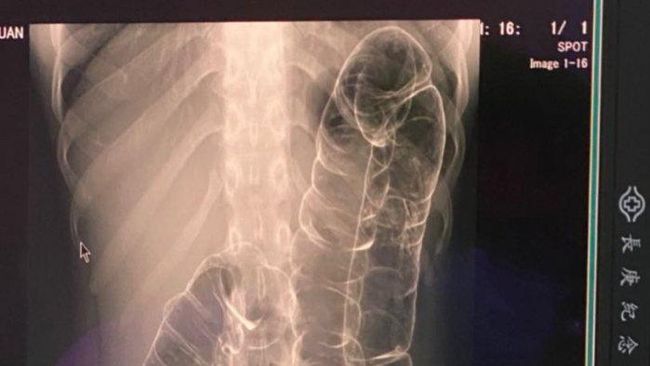

Foto: Dcard

Viral di media sosial foto rontgen seorang pasien dengan usus yang naik hingga daerah dada. Dinarasikan, pasien tersebut tidak buang air besar (BAB) selama satu bulan.

Ternyata, foto rontgen itu merupakan hasil rontgent dari seorang wanita di Taiwan pada 2020. Pasien merupakan seorang wanita berusia 23 tahun yang menderita sembelit parah.

Akhirnya ia pun pergi ke dokter untuk mengecek kondisinya. Ternyata ia mengalami pergeseran usus besar.

"Usus besar saya sangat panjang dan memanjang hingga ke atas," ceritanya.

Selain itu terungkap juga bagian terakhir dari usus besarnya tidak memiliki kerutan yang kemungkinan disebabkan penumpukan kotoran selama bertahun-tahun.